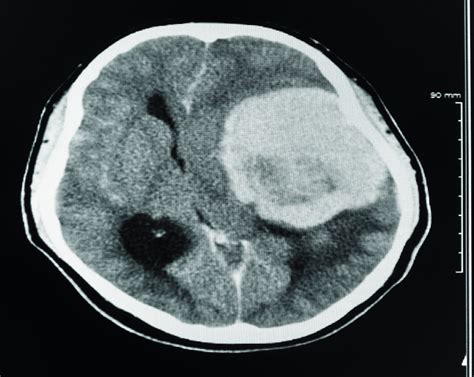

Doctors often order this scan if they suspect an abnormality such as a tumor, cyst, or inflammation. By visualizing the physical landscape of the brain, medical experts can identify the location, size, and shape of potential growths, which is crucial for determining the next steps in a clinical treatment plan.

Once the scan is complete, a radiologist—a doctor specialized in interpreting medical images—will analyze the data. They look for masses, swelling, or structural anomalies that could indicate cancer or other conditions. The results are typically sent to your primary physician or neurologist, who will then discuss the findings with you during a follow-up appointment.

It is important to remember that a "positive" finding on a scan does not automatically confirm cancer. Many non-cancerous conditions, such as benign cysts or infections, can mimic the appearance of a tumor. Further diagnostic procedures, such as a biopsy or an MRI with gadolinium contrast, may be required to reach a definitive diagnosis.